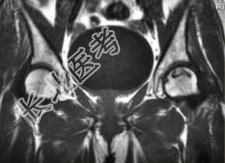

- [材料题] 男性,47岁。左髋部疼痛及压痛6个月,“4”字试验阳性。左髋关节内、外旋活动受限。检查提示:左髋关节活动轻度受限,大腿上部轻压痛。血常规检查正常。髋关节CT及MRI如下图。

- 多项选择题1.根据髋关节CT和MR影像,你认为此病例的影像学表现有

A、CT检查未见异常

B、左侧股骨头内可见线样高密度影

C、左股骨头塌陷变扁,其内可见条带状硬化

D、左股骨头内见蜿蜒走行的T

、T

低信号条带影E、左髋关节腔内可见弧线状长T

、长T

信号F、左髋关节间隙变窄

- 多项选择题2.对本病例,你首先考虑的诊断是

B、左股骨头缺血性坏死

F、左髋关节腔积液